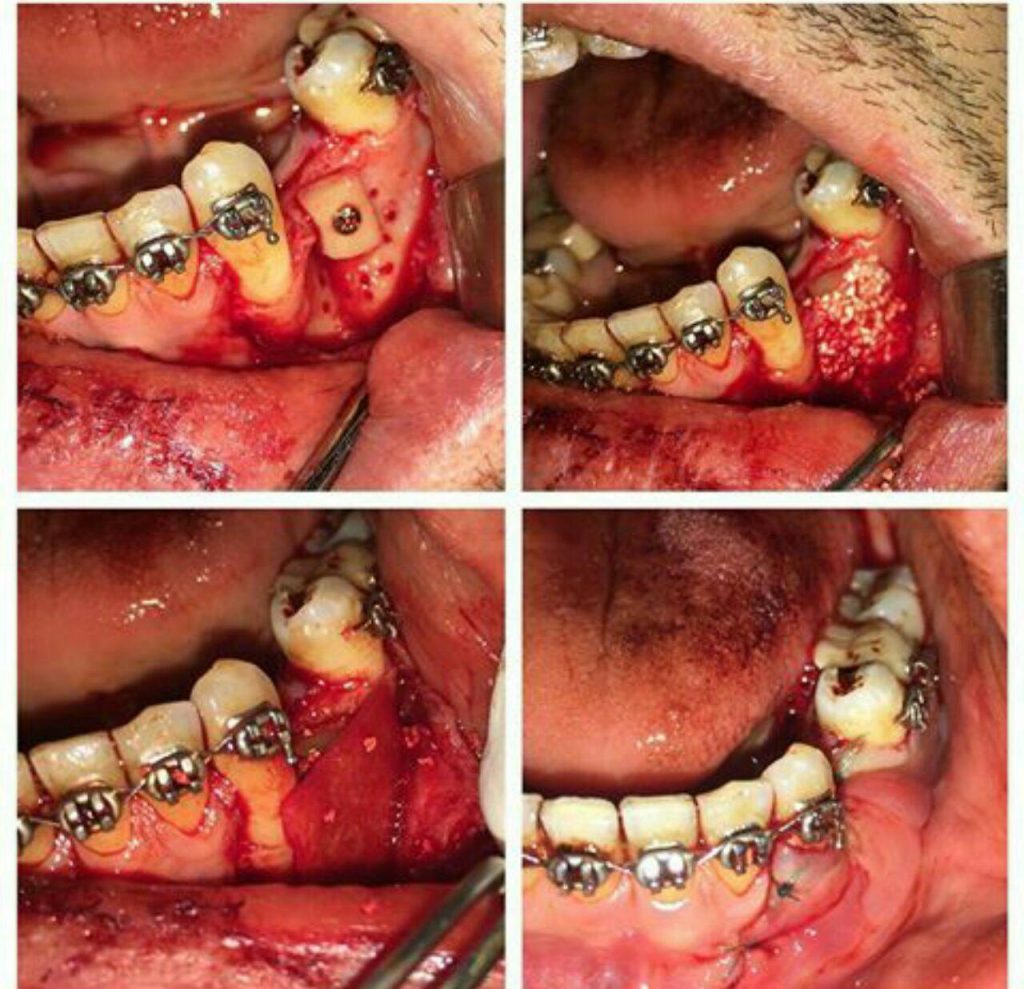

كلينيك تخصصي دندانپزشكي دكتر حامد كرامت

جراح دندانپزشك

متخصص بيماريهاي دهان، فك و صورت

فلوشيپ ايمپلنت از ICOI آمريكا

گواهينامه ايمپلنت و زيبايي از دانشگاه UCLA آمريكا